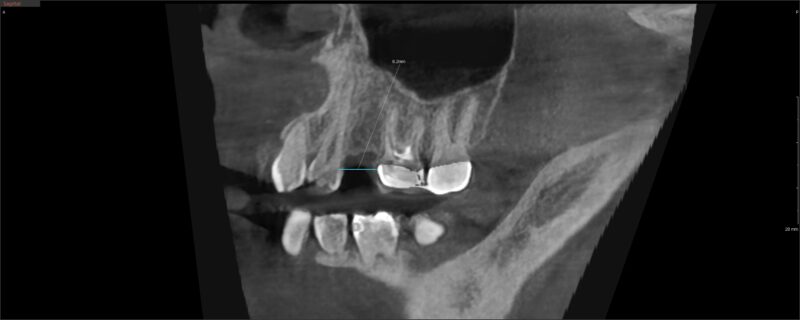

I have another case here with a buccal defect on tooth # 13. Pt has been wearing a flipper for over 10 years.

Looking at the insufficient B-L width at 4.8mm, I’d like to do a ridge augmentation (mini-sausage technique) and two stage this ( I really dont want to do a ridge split) where I would:

1. crestal incision with 2 vertical releasing flaps ensuring that the base is thicker.

5. Coronally position the flap to get primary closure and suture using an internal fixation, horizontal matress, and interrupted sutures where the vertical releases are. I don’t see how I can coronally position and get primary closure if I don’t do 2 vertical releasing incisions. Are the incision lines in the right place?

2) Especially if you are newer to this, I would probably want to move those vertical releasing incisions further away from the graft site. You can hop over to the next tooth. The idea is to keep your cuts away from your graft sites.